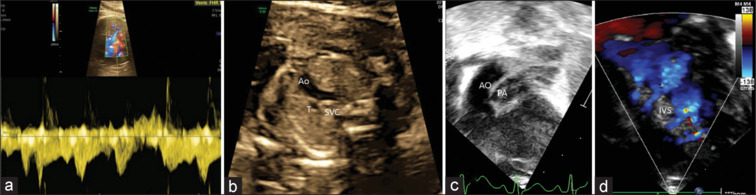

大多数产前发现d型大动脉转位并室间隔完整(TGA-IVS)的新生儿术前病程相对标准,但一些卵圆孔(FO)或动脉导管受限的患者出生后容易出现严重的低氧血症,在出生后数小时内死亡风险显著。含氧血和缺氧血混合不良会导致严重的紫绀和死亡。我们报告了两名产前诊断为TGA-IVS的新生儿,他们表现出明显的去饱和,需要紧急气囊房间隔造口术(BAS)。在这两个病人中,混合的结果是不充分的;导管支架植入必须恢复氧合。这些病例强调了产前识别TGA-IVS胎儿的高危特征的重要性,如限制性FO或导管收缩。尽管在解剖学上有足够的BAS,但这些婴儿中有一小部分混合不充分,可以在手术前通过导管支架植入进一步稳定。

Most neonates with prenatally detected d-transposition of great arteries with intact ventricular septum (TGA-IVS) have a relatively standard preoperative course, but some patients with restrictive foramen ovale (FO) or ductus arteriosus tend to have severe hypoxemia after birth, posing a significant risk of mortality in the first few hours after birth. Poor mixing of oxygenated and deoxygenated blood leads to severe cyanosis and death. We present two prenatally diagnosed neonates with TGA-IVS who presented with significant desaturation, necessitating emergency balloon atrial septostomy (BAS). In both patients, the resultant mixing was inadequate; ductal stenting had to be resorted to restore oxygenation. These cases highlight the importance of prenatal identification of high-risk features, such as restrictive FO or ductal constriction, in fetuses with TGA-IVS. A small proportion of these babies who have inadequate mixing despite an anatomically adequate BAS can be further stabilized before surgery by means of ductal stenting.